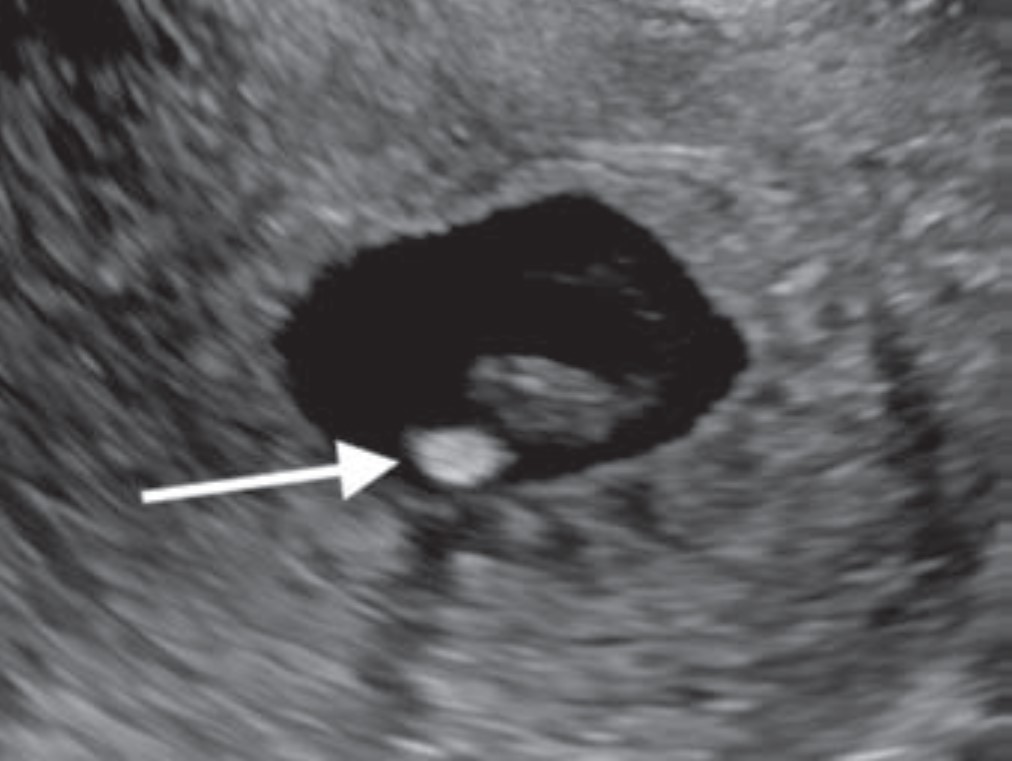

First-Trimester OB Imaging in the Emergency Setting

Radiologists play a key role in detecting early pregnancy, assessing cardiac activity and gestation location, as well as evaluating for complications in the acute setting. Knowledge of potential technical errors in image acquisition and an understanding of possible ectopic implantation locations are also necessary to optimize care of the pregnant patient in the first trimester. “First-Trimester OB Imaging in the Emergency Setting” reviews the pearls and pitfalls of first-trimester ultrasound—early pregnancy development, early pregnancy loss, intrauterine pregnancy of unknown location, ectopic pregnancy—applying the 2024 Society of Radiologists in Ultrasound Consensus Conference’s recommended lexicon throughout (Fig. 5).